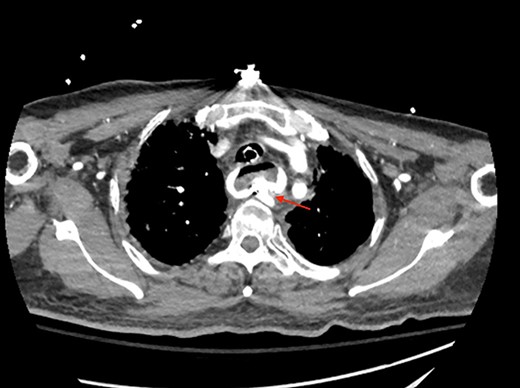

A 71-year-old male with past medical history of type 2 diabetes and hypertension presented to the emergency department at St. Joseph’s University Medical Center with severe respiratory distress. On nonrebreather, the patient’s oxygen saturation was 49%. The patient was subsequently intubated. Evaluation revealed pneumonia secondary to COVID-19 leading patient to be intubated on ventilator support for 4 weeks. During this time patient was maintained on enteral feeding through nasogastric tube, and was on gastrointestinal prophylaxis Protonix 40 mg daily for the duration of his admission. Ultimately, the patient made full recovery and was sent home; however, approximately 3 weeks later, he presented to the emergency department due to syncope. The patient experienced large-volume bright red hematemesis. He became hypotensive and was transfused three units of packed red blood cells and started on pressors. The patient was intubated and transferred to the intensive care unit (ICU) with acute blood loss anemia and hypovolemic shock. Here, an esophagogastroduodenoscopy (EGD) was performed revealing midesophageal bleed (Fig. 1). Hemostasis was achieved with clipping; however, post-procedurally, the patient again became hypotensive. Repeat EGD showed a nonbleeding esophageal ulcer with three clips in good position (Fig. 2). Computed tomography (CT) angiogram of the thorax was performed revealing an actively bleeding aberrant right subclavian artery perforating into the esophagus (Figs 3 and 4). The right subclavian artery was noted to be of normal caliber without ectasia or aneurism and the esophagus was free of any other pathology. Thoracic and vascular surgery were consulted; however, the bleed was deemed of nonsurvivable pathology due to comorbidities and current clinical status. Ultimately, the family of the patient decided to withdraw care and the patient passed.

CT thoracic angiogram showing actively bleeding aberrant right subclavian artery perforating into the esophagus (red arrow).

CT thoracic showing the arch of the aorta with the take-off of the right subclavian artery (red arrow) distal to the left subclavian artery.